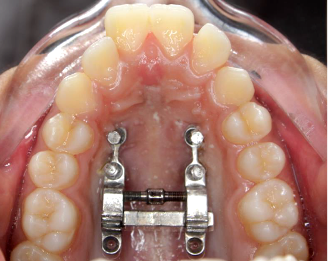

Fig.1 Bone-bone anchored designThe support arms can be temporarily bonded with composite to stabilize the expander for TAD insertion and cut off afterwards

Fig.2 Bone-bone anchored designThe support arms can be temporarily bonded with composite to stabilize the expander for TAD insertion and cut off afterwards